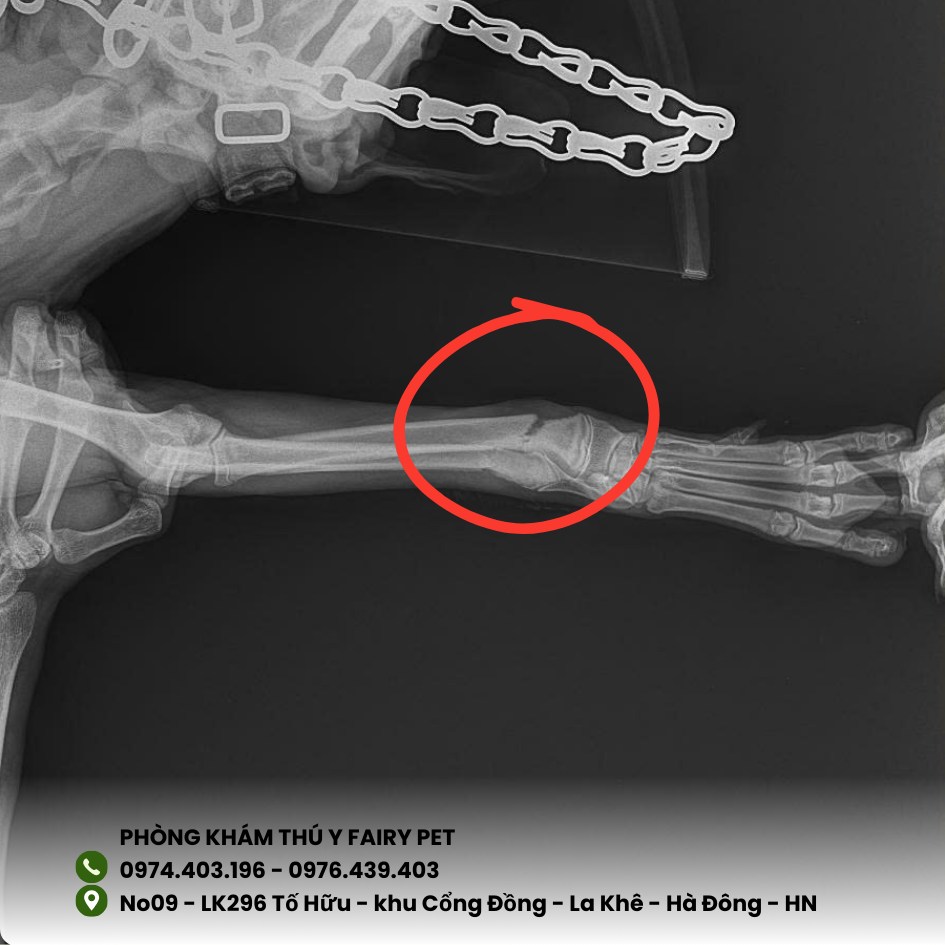

Khi chẳng may thú cưng bị 𝒈𝒂̃𝒚 𝒙𝒖̛𝒐̛𝒏𝒈 khiến nhiều Sen lo lắng.

👉 Thông thường, với chó mèo, thời gian lành xương dao động 3–8 tuần tùy theo vị trí gãy, độ tuổi và cách chăm sóc sau điều trị.

🩻 𝑪𝒉𝒂̂̉𝒏 đ𝒐𝒂́𝒏 chính xác 𝒃𝒂̆̀𝒏𝒈 𝑿-𝒒𝒖𝒂𝒏𝒈

🩹 Đ𝐢𝐞̂̀𝐮 𝐭𝐫𝐢̣ đúng cách (bó bột hoặc đóng đinh cố định)

✅ Chụp X-quang – xác định chính xác tình trạng gãy xương

✅ Điều trị an toàn: bó bột, đóng đinh cố định tùy mức độ